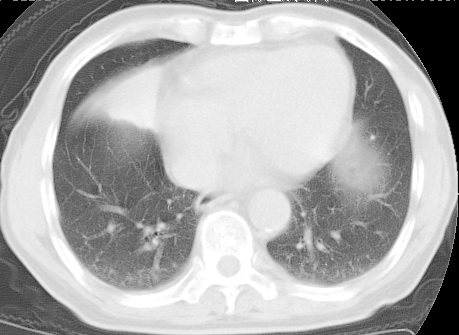

标题: CT24032:男65岁,咳嗽,吸烟20余年,无发热,咳痰 [打印本页]

标题: CT24032:男65岁,咳嗽,吸烟20余年,无发热,咳痰

考虑右肺中叶不张,请大家发表意见

右肺中叶不张、肺门轮廓增大,占位不除外;建议增强,必要时支气管镜详查。

右肺中叶支气管闭塞,中叶肺不张,右侧肺门见肿块影。中心型肺癌的可能大。建议支气管镜检查。

右中叶体积明显缩小,且其支气管未显示,先考虑:中心型肺癌班右中叶肺不张。

建议:支气管镜检查。

考虑右肺中叶中央型肺癌并右肺中叶肺不张;建议:行纤支镜检查。

右肺门旁类圆形肿块影,右肺中叶不张,建议纤支镜检查。

1右肺门旁类圆形肿块影,右肺中叶不张,建议纤支镜检查

2右侧胸膜增厚,右侧叶间胸膜区钙化

3右肺下叶小囊状透亮影考虑肺气肿

平片就可以诊断右肺中叶不张,做CT就是要找原因!中叶支气管开口不清,建议支气管镜检查。